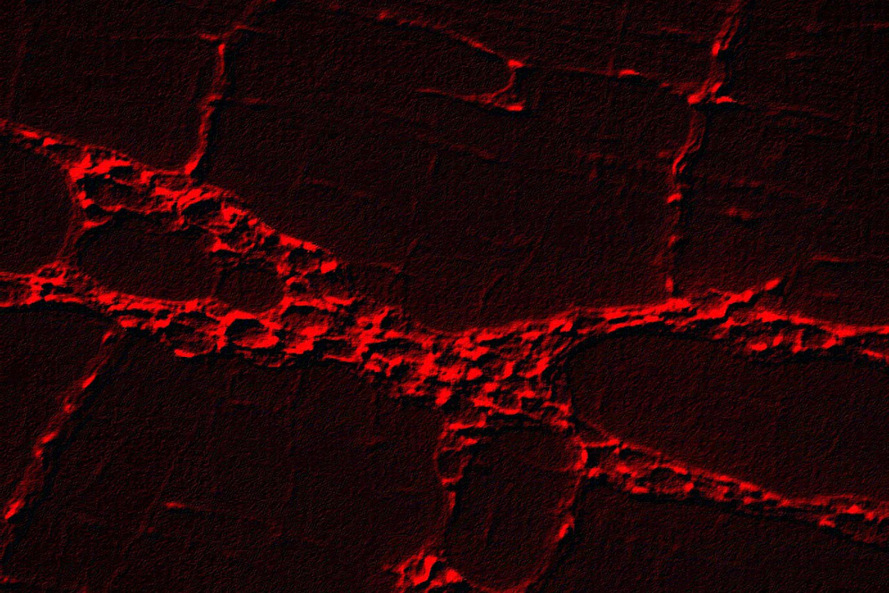

Pesquisadores da Universidade Estadual de Maringá (UEM) identificaram de forma automática a presença de três doenças crônico-degenerativas a partir do reconhecimento de padrões em imagens de células do sistema nervoso entérico de animais de laboratório. O estudo, considerado inédito, mostra que o método proposto é capaz de reconhecer corretamente a ocorrência das doenças com taxas de 89,3% para artrite reumatoide, 95,13% para diabetes e 98,45% para tumor de Walker (câncer).

O orientador Gustavo Yandre Costa, professor no Departamento de Informática (DIN) e membro do Laboratório de Sistemas Interativos e Inteligentes da UEM, diz que a pesquisa partiu da hipótese de que poderia haver padrões ligados ao conteúdo visual dessas imagens, que seriam úteis para reconhecer essas doenças. “A partir disso, exploramos principalmente informações ligadas ao conteúdo de textura dessas imagens e utilizamos alguns algoritmos de classificação bastante conhecidos na literatura de inteligência artificial”, afirma.

Os pesquisadores avaliaram amostras de células de glia entérica. Foram avaliadas características obtidas com o método tradicional de engenharia e características aprendidas automaticamente com o uso de modelos profundos de aprendizagem. “Além da contribuição técnica para as análises pré-clínicas, visamos incentivar o desenvolvimento de técnicas e metodologias inéditas, capazes de apoiar a solução de problemas desafiadores existentes nas práticas laboratoriais”, afirma Gustavo.